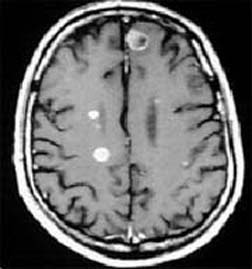

To really understand how ms affects the cells, it helps to have a little context on how nerve cells ms lesions are an important sign of ms and can show up directly on an mri scan.

Magnetic resonance imaging (mri) usually reveals many more lesions than the ct multiple sclerosis: Waking up day after day knowing you are stricken with ms that gradually drags you, healthy young person, toward chronic illness and. Magnetic resonance imaging (mri) usually reveals many more lesions than the ct multiple sclerosis: Learn the causes, early signs, and symptoms.